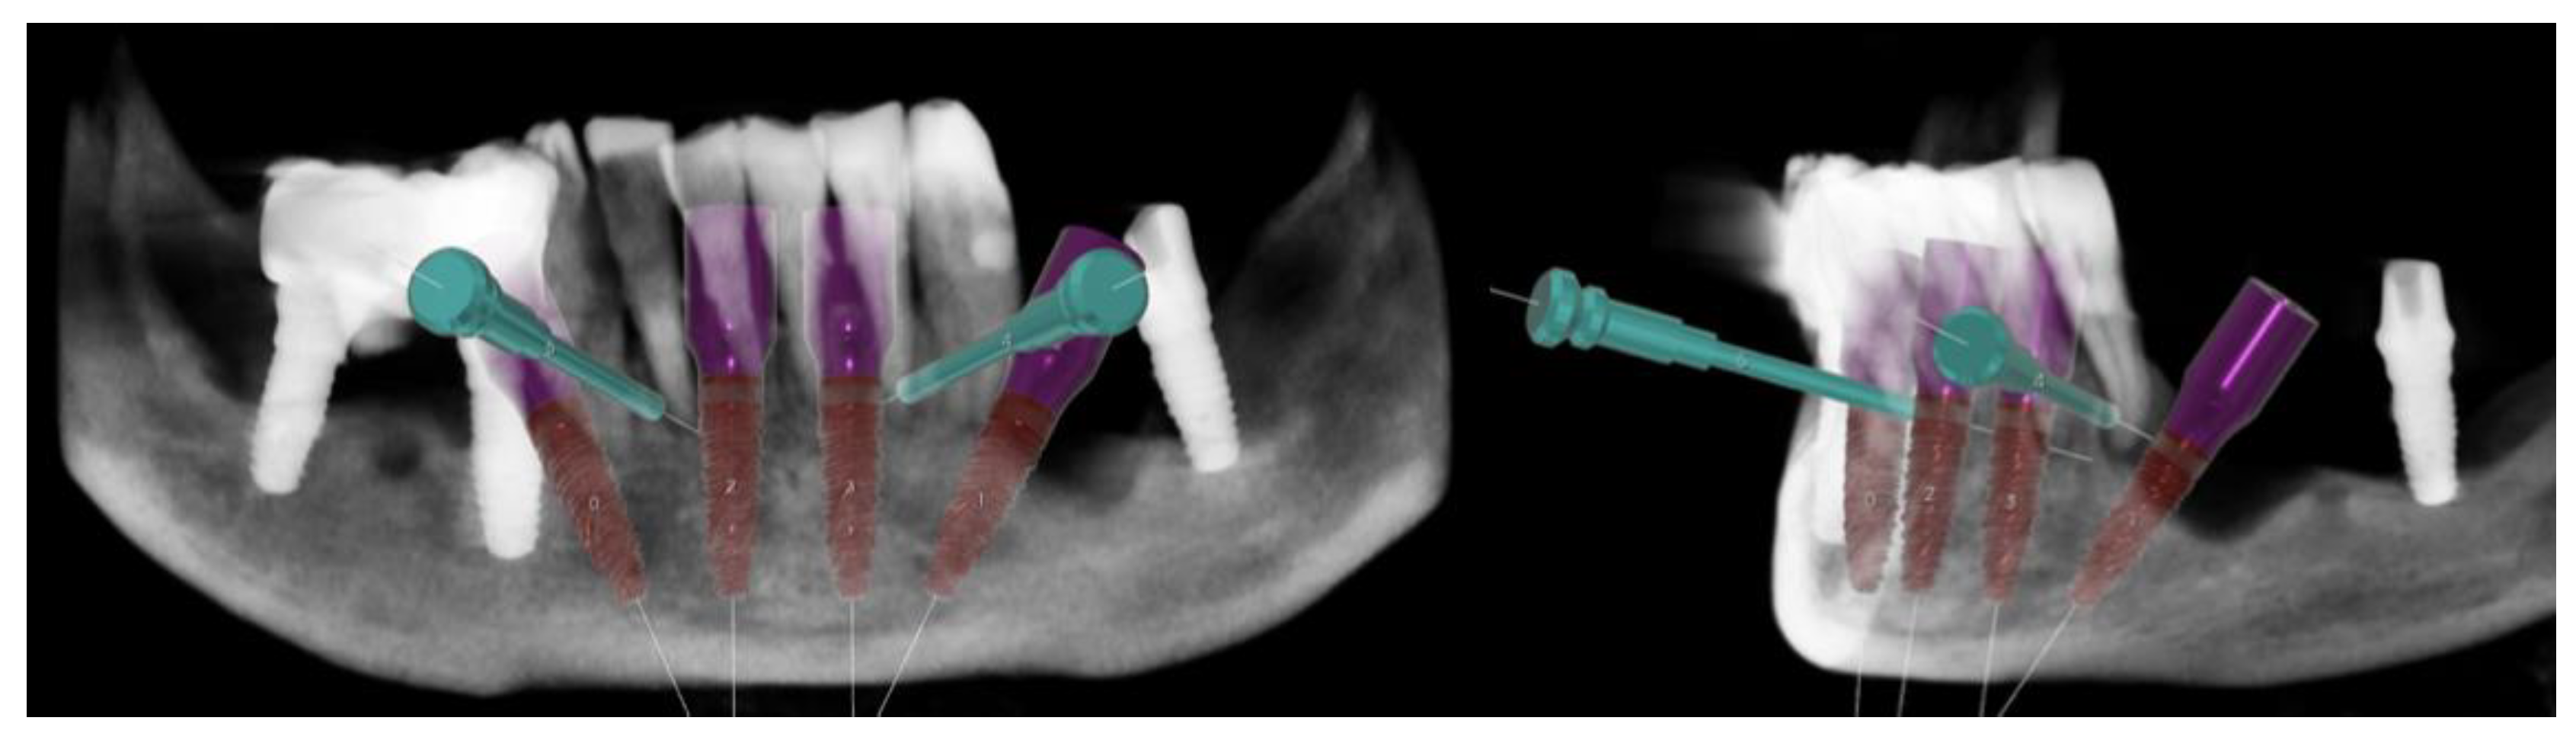

2.1. Planning

Surgical Guide

2.4. Surgery